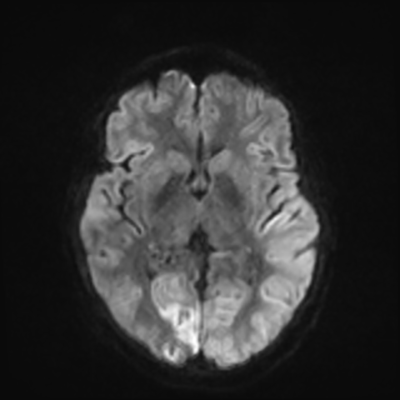

MRI brain (DWI)

You can clearly see diffuse cortical and basal ganglia diffusion restriction, and that of his deep cerebellar nuclei as well. The right occipital lobe abnormalities are a little more prominent, but then you remember that he is known to have had a right occipital stroke weeks ago.

In reviewing his data, you know that he doesn't have any of the strong predictors of a poor neurologic prognosis. However, based on these findings on MRI, along with the absent reactivity on cEEG, you are able to tell the primary team and the patient's family that he is likely to have a poor prognosis, based on these multiple moderate predictors. Recovery is not completely impossible-- there is more uncertainty with this prognostication than if we were able to get SSEPs-- but you're very worried about his outlook and that any potential recovery would require a very protracted rehabilitation period. Given his high cervical cord injury level, tracheostomy would be required anyway. So, it comes down to whether his family thinks he'd want to pursue these aggressive measures.